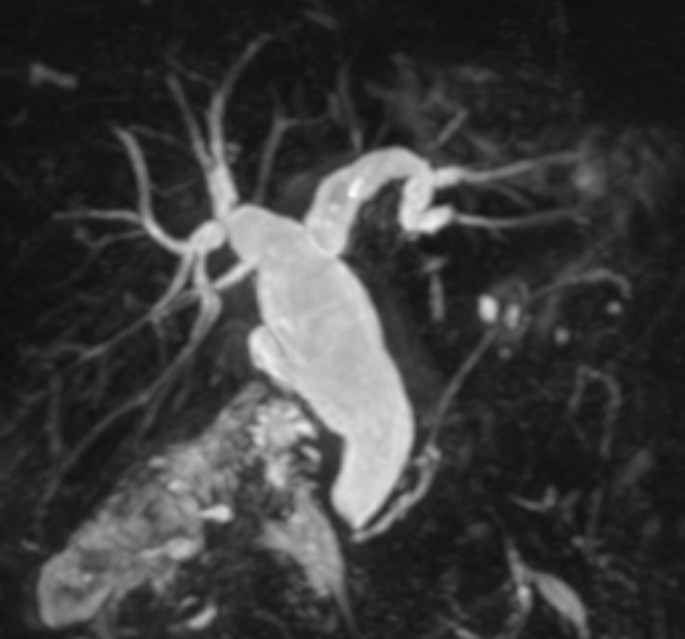

МРТ изображения выполнены 229 больным на томографе «New Intera» с напряженностью магнитного поля 1,5 Т. Пациенты были обследованы в положении на спине, при задержке дыхания с использованием катушки для тела. Сначала выполняли обычные аксиальные Т1-, Т2-взвешенные и коронарные Т2-взвешенные МР изображения верхнего отдела брюшной полости с использованием последовательности Turbo Spin-Echo (TSE) и дополнительные аксиальные Т2- и/или Т1-взвешенные последовательности с подавлением жира (SPIR). Обычные аксиальные изображения служили исходными для выполнения у 211 пациентов МРХПГ. Коронарные МРХПГ изображения были выполнены с использованием multislice heavily Т2-взвешенной TSE последовательности (TR=2 000 мс, ТЕ=700 мс). При невозможности выполнить задержку дыхания использовался режим respiratory-triggering, чтобы уменьшить артефакты от дыхательных движений пациента. После получения исходных МРХПГ изображений были построены 3D-реконструкции с использованием алгоритма проекций максимальной интенсивности (MIP). Общее время получения МР изображений составило приблизительно 30 минут. МРХПГ обеспечила высокую (93,1%) достоверность диагностики заболеваний желчных путей, печени, поджелудочной железы и главного панкреатического протока. При этом метод позволил у 201 (81,38%) пациента определить уровень, протяженность и причину обтурации протоковой системы (Рис. 7).

Рис. 1 МРХПГ. Конкремент в общем печеночном протоке.

Рис. 2 МРХПГ. Внутрипеченочная желчная гипертензия, гипертензии в протоке поджелудочной железы за счет образования головки поджелудочной железы.

Рис. 3 МРХПГ. Желчная гипертензия. Рубцовая стриктура проксимального отдела общего желчного протока.

Рис. 4 МРХПГ. Дефекты наполнения (конкременты) в просвете общего печеночного и общего желчного протоков.

Рис. 5 МРХПГ. Внутрипеченочная желчная гипертензия, гипертензии в протоке поджелудочной железы за счет отека головки поджелудочной железы (псевдотуморозный панкреатит).

Рис. 6 МРХПГ. Желчная гипертензия. Объемное образование большого дуоденального сосочка.